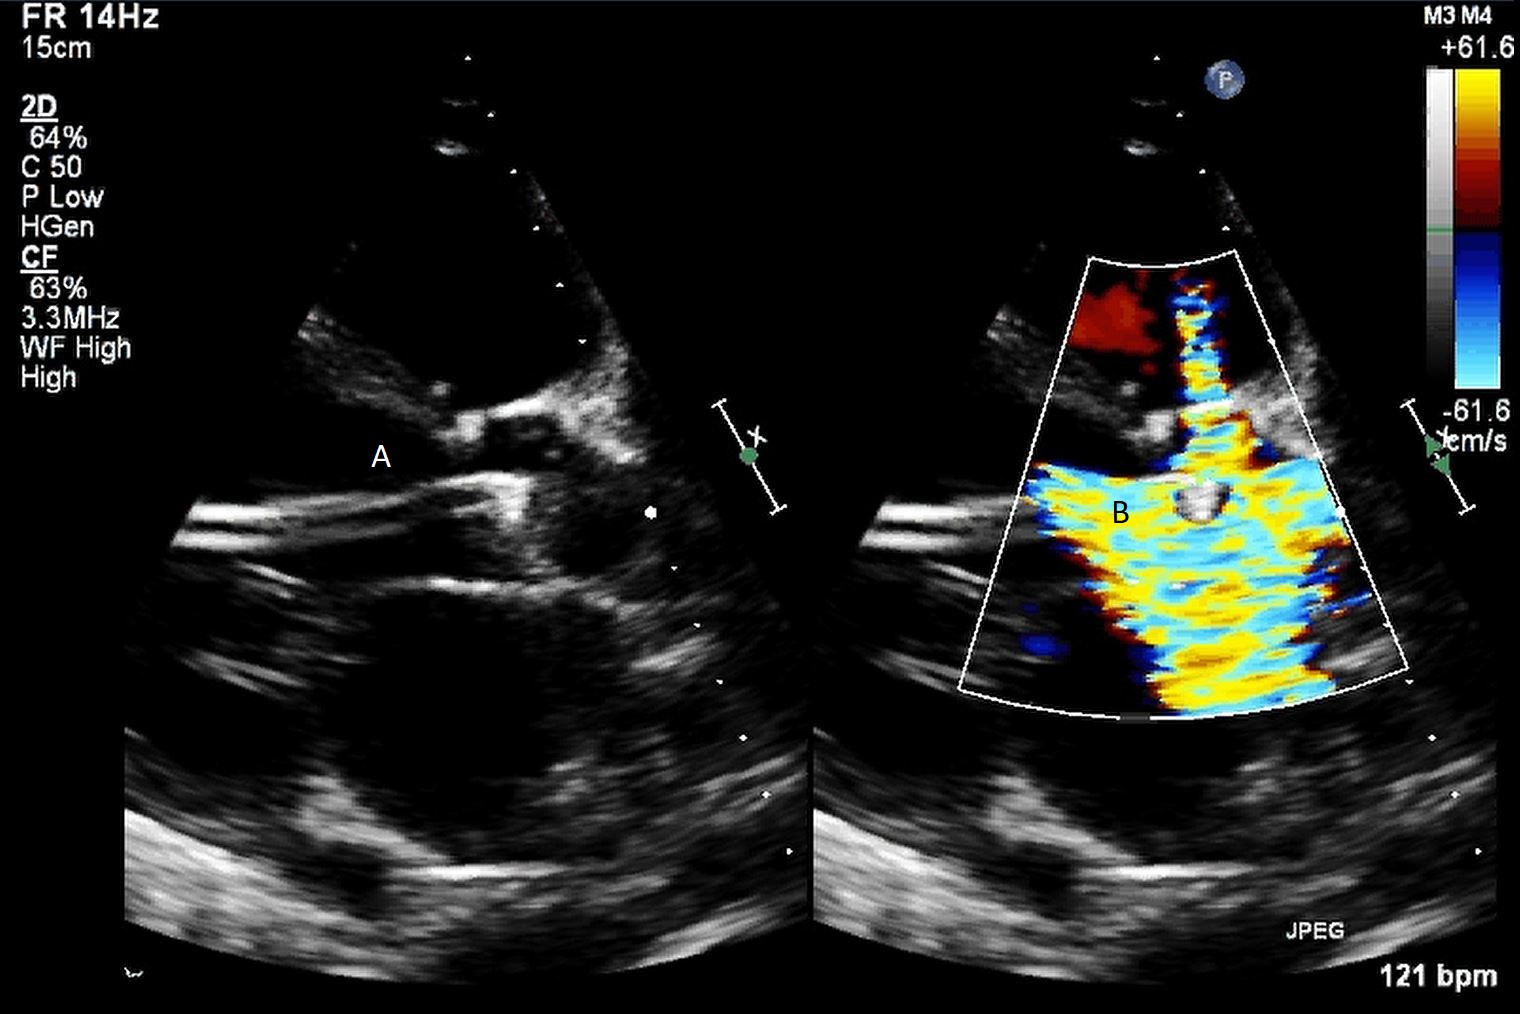

Both TTE and TEE can help with ideal positioning of the Impella (Figs. 5,6). The distance from the aortic valve to the Impella inlet should be measured. This should ideally be 3.5–4 cm for all Impella devices except for the Impella 5.5 for which it is 5 cm [15] (Fig. 7). The outlet should be 1.5–2 cm above the sinuses of Valsalva. The catheter should be angled towards the LV apex and away from the septum and mitral valve. The positioning of both the inlet in the LV cavity and the outlet above the aortic valve should be confirmed. Color flow doppler imaging can help confirm this positioning as a mosaic pattern will be visualized near the inlet and outlet ports on spectral doppler (Fig. 8). Real-time 3D echocardiography can also be used to help in visualizing Impella positioning relative to other anatomical structures (Fig. 9). After placement of the Impella, the aortic and mitral valves should be interrogated for any new or worsening regurgitation or dysfunction [16]. TEE can also help identify additional complications of Impella placement including pericardial effusion or LV free wall rupture [17].

Fig. 8.A parasternal long axis view on a transthoracic echocardiogram zoomed up on the aortic valve. Color flow imaging demonstrates a mosaic pattern at the Impella outlet, confirming its position as being above the aortic valve. (A) Impella outlet. (B) Mosaic pattern at Impella outlet on color flow doppler.